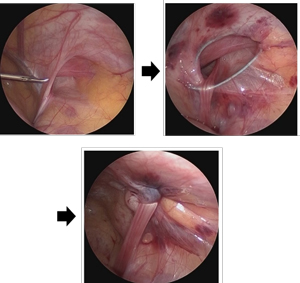

当科では、従来の手術方法 (従来法)に加え、性別に関係なく積極的に腹腔鏡手術 (LPEC法)を取り入れております。従来法でも、鼠径部の創は1。5cm程度と小さく、全く目立ちません。腹腔鏡手術の創は5mm程度でさらに小さく、身体への負担も非常に少ないです。

また、陰嚢水腫などに対しても積極的に腹腔鏡手術を取り入れており、良好な成績をおさめています。